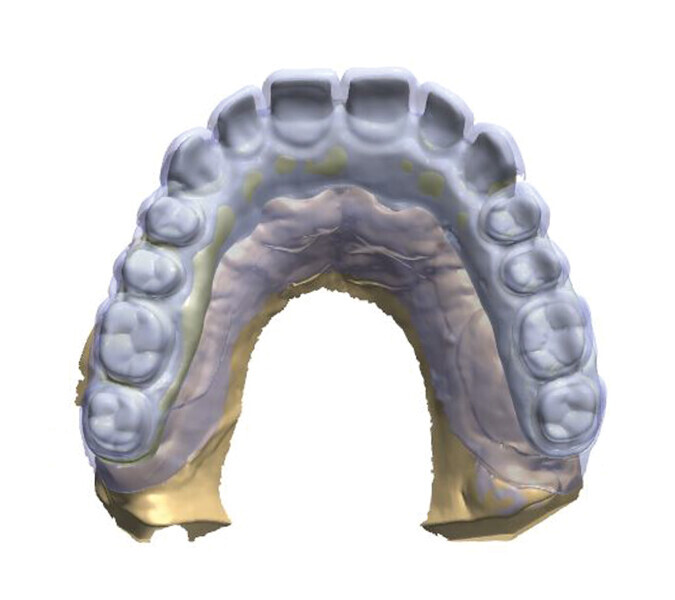

Fig. 2: Design of the construction with the transparency mode on.